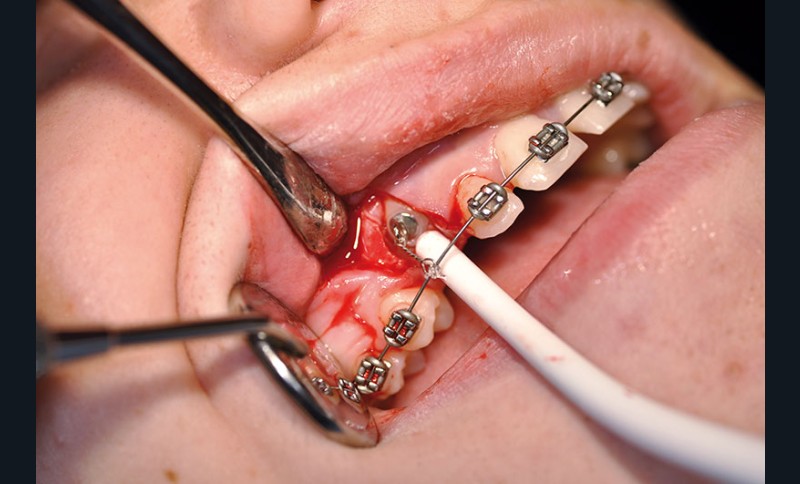

chirurgie à visée orthodontique : extractions de dents de sagesse, dégagement de dents incluses, poses de mini-vis et mini-plaques…